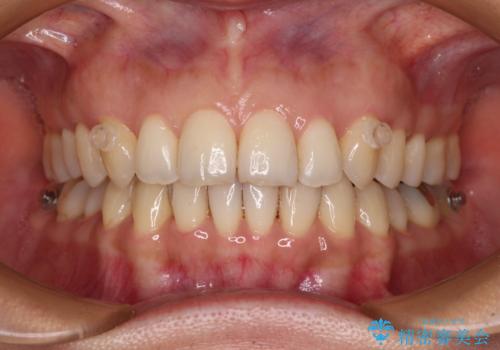

矯正治療の後戻り インビザライン・ライトによる矯正治療

- 矯正治療の後戻りを気にして来院された患者様です。

後戻りは軽微であったので、インビザライン・ライトにより矯正治療を行うこととしました。